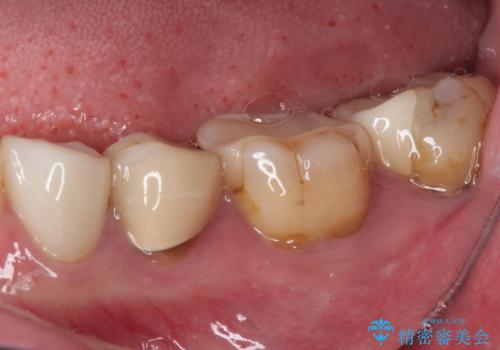

痛みが引いた後、不揃いな見た目で気になっていた左下の奥歯とともにオールセラミッククラウンにて補綴治療を行うこととしました。

右上の歯は、第二小臼歯の初回処置後に痛みを感じなくなったため、他の歯については問題なしと診断しました。

将来ホワイトニングをされるとのことで、前歯よりもやや白い色合いのオールセラミッククラウンを選択されました。